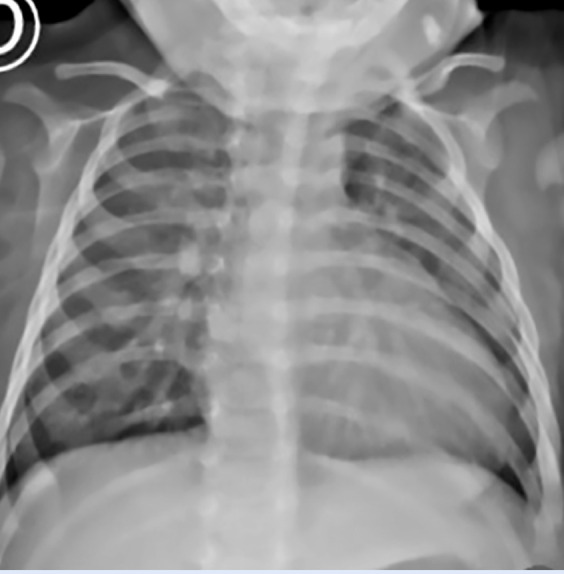

主动脉肺窗是一种罕见的先天性心脏缺陷。无其他相关异常的孤立性主动脉肺窗占所有病例的25%。手术封闭一直是,并且仍然是许多心血管中心的黄金标准。然而,经皮闭合已经成为一种可行的选择,使用各种类型的闭塞装置,根据缺损的形态、大小和边缘来选择,以尽量减少并发症,如瓣膜干扰或冠状动脉口梗阻。我们报告一例婴儿与孤立的主动脉肺窗成功治疗经皮封闭使用肌肉室间隔缺损闭塞装置,没有并发症。术后48小时患者出院。

The aortopulmonary window is a rare congenital heart defect. Isolated aortopulmonary window, without other associated anomalies, accounts for up to 25% of all cases. Surgical closure has long been, and remains, the gold standard in many cardiovascular centres. However, percutaneous closure has emerged as a viable alternative using various types of occluder devices, selected based on the morphology, size, and rims of the defect to minimise complications such as valvular interference or coronary ostial obstruction. We report the case of an infant with an isolated aortopulmonary window successfully treated with percutaneous closure using a muscular ventricular septal defect occluder device, with no complications. The patient was discharged 48 hours after the procedure.